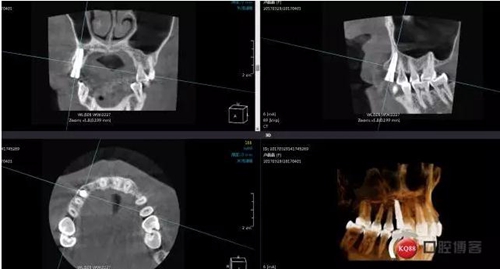

患者右上二缺失,CT示唇腭向骨量不足,右上3為乳牙滯留且骨量足設(shè)計(jì)右上三即拔即種手術(shù)

術(shù)前ct